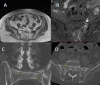

A. T1 weighted MRI axial views of a fatigue sacral fracture (case 1 in Table 1). B. STIR MRI coronal view of the same fracture (case 1 in table 1). Fracture is classified according to Kaeding Miller classification as grade III. C coronal CT view of bilateral sacral fractures of case 2 (Table 1), D axial CT view of the same fractures. Both fractures are classified as grade IV according to Kaeding Miller classification.